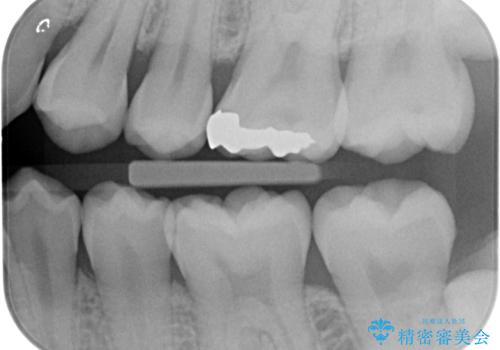

- 金属アレルギーが気になるとの事で来院。

拡大鏡下で銀歯を外し、セラミックの詰め物で修復しました。

- e-maxインレー 7.7万費用は治療当時の料金となります